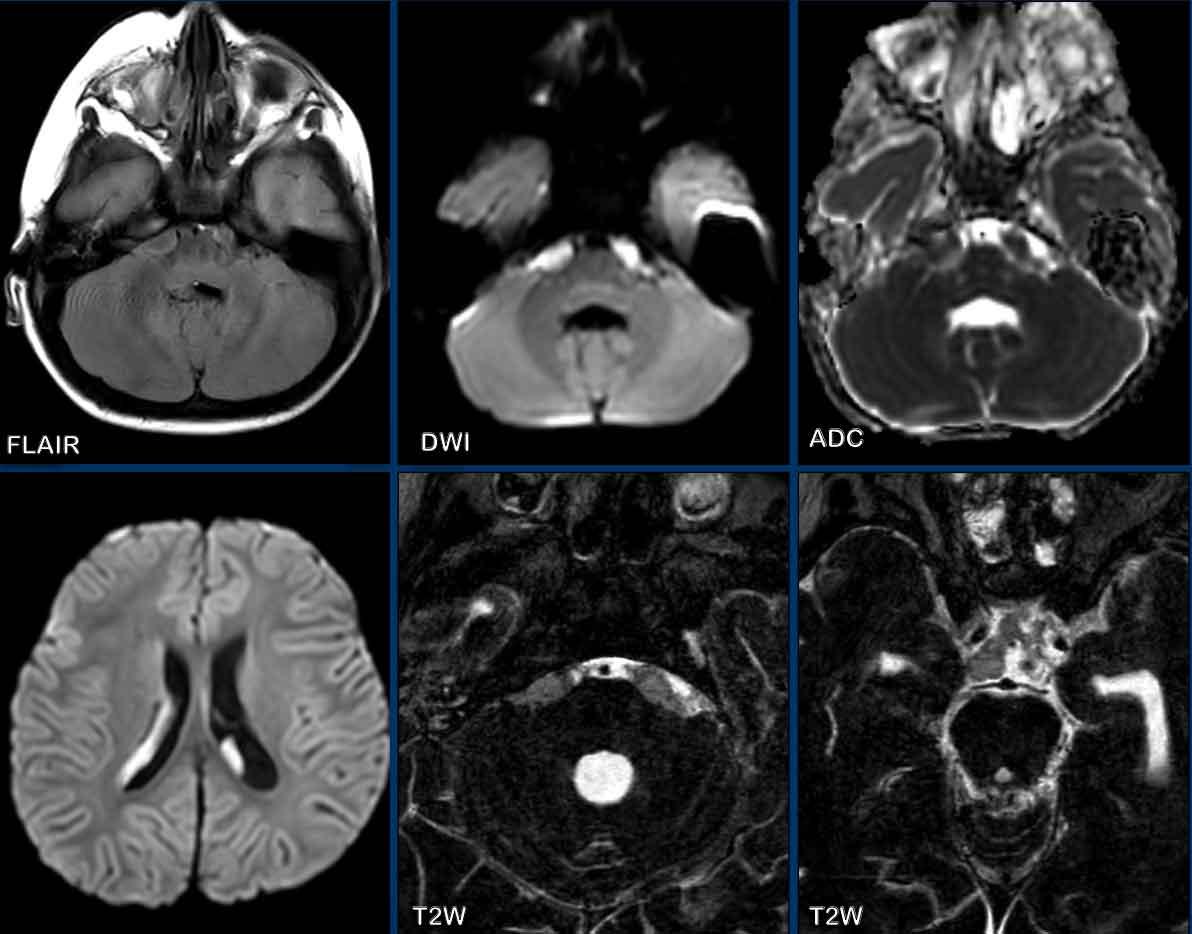

Đây là hình ảnh của một trẻ 2 tuổi, nhập viện với sốt, liệt thần kinh vận nhãn ngoài (dây VI) và cuối cùng mất ý thức.

Hình ảnh

Có xóa mờ bể trước cầu não trên FLAIR kèm hạn chế khuếch tán.

Có tín hiệu tăng trên DWI tại các não thất hai bên, phù hợp với mủ.

Hình ảnh T2W độ phân giải cao cho thấy mất tín hiệu tăng trong các bể dịch não tủy và khoang dưới nhện, do mủ đặc.

Chẩn đoán cuối cùng

Viêm màng não và viêm não thất do Haemophilus influenzae type B.